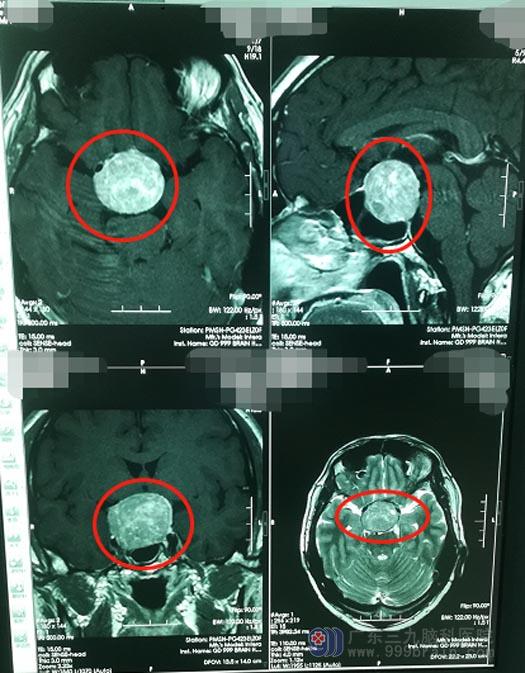

第二天,吴先生就急急忙忙地赶到了广东三九脑科医院神经外五科,进一步的脑部检查发现:鞍区示一类圆形占位性病变,呈长T1不均长T2异常信号影,增强(1.5T)增强后病变明显强度,范围约为4.0cm×3.5cm×3.3cm,视交叉受压上抬显示不清,邻近双侧颈内动脉局部稍包埋;诊断为鞍区占位性病变,考虑垂体大腺瘤。